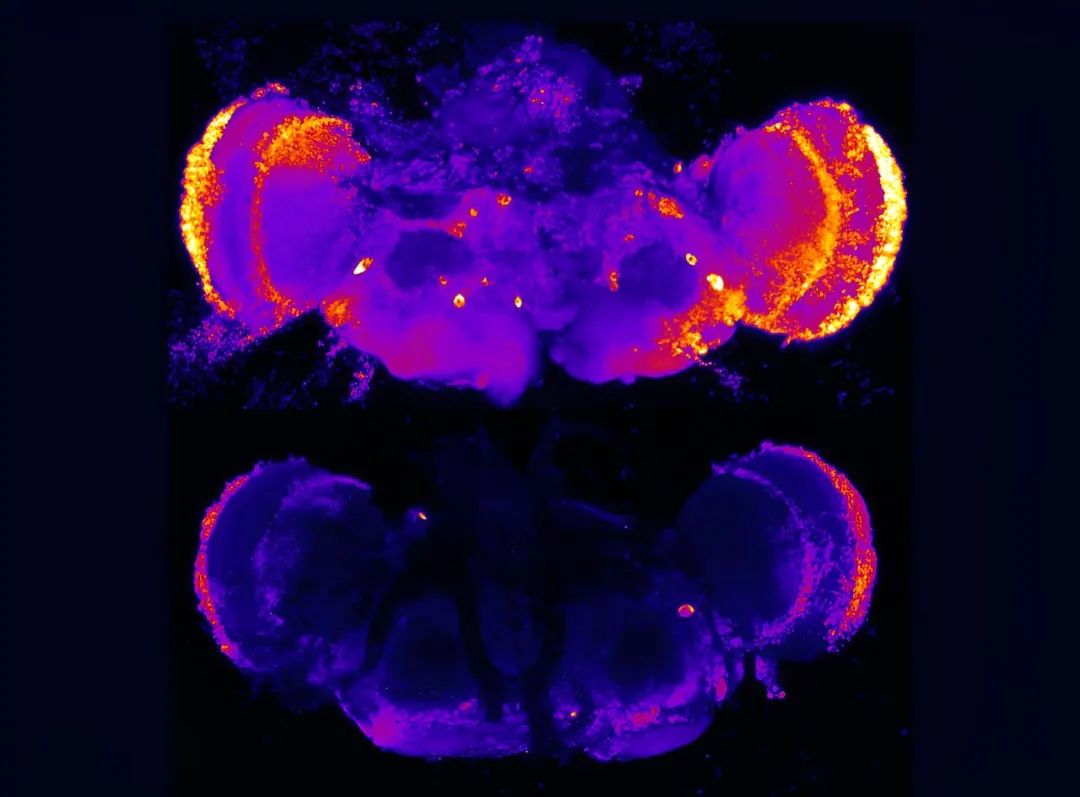

早老素基因PSEN1的突变会导致人类和经过基因改造以携带该基因的果蝇出现阿尔茨海默病的早期症状。Penn State 研究人员领导的一项新研究揭示,在果蝇中破坏硫酸乙酰肝素修饰蛋白可以抑制神经元死亡,并纠正阿尔茨海默病和其他神经退行性疾病早期常见的其他细胞缺陷。图中展示的是用标记物染色的完整果蝇大脑,该标记物指示细胞死亡——颜色越亮表示细胞死亡越多。上方:PSEN1基因缺陷的果蝇(阿尔茨海默病模型)显示出高水平的细胞死亡。下方:通过破坏硫酸乙酰肝素修饰蛋白而得到挽救的果蝇大脑

然后,研究人员在一种阿尔茨海默病动物模型(早老素蛋白缺陷的果蝇)中评估了硫酸乙酰肝素修饰蛋白的作用。早老素突变会导致人类和果蝇都出现早发性疾病,缺陷早老素会导致细胞死亡和大脑退化。在早老素缺陷的果蝇中,降低硫酸乙酰肝素链的功能抑制了神经元的死亡,并纠正了其他细胞缺陷。研究人员表示,这些结果与人类遗传学研究的最新进展直接相关。